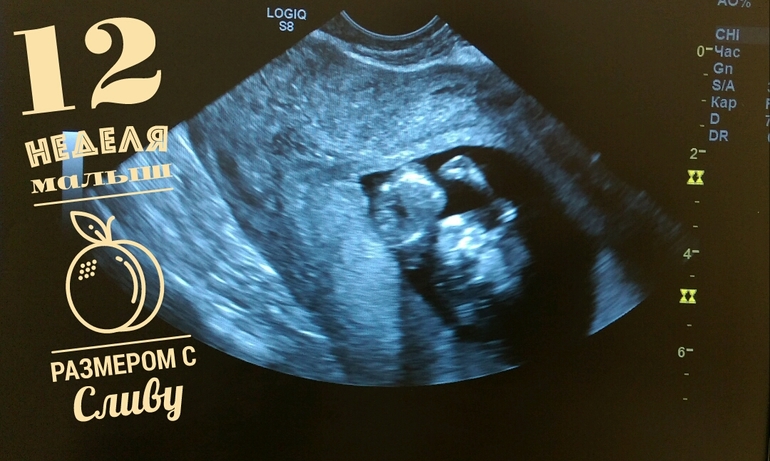

По узи, срок 12,2. СБ 154 уд/мин. КТР 57 мм, БПР 18,0 мм. ТВП 1,0

ПДР по узи на 17/10/2017. Расположение хориона по задней стенке, высоко. Как и с дочкой. Значит животик будет снова аккуратный, что не может не радовать)

Фото вывели на монитор неудачное, мне непонятно где голова и тело